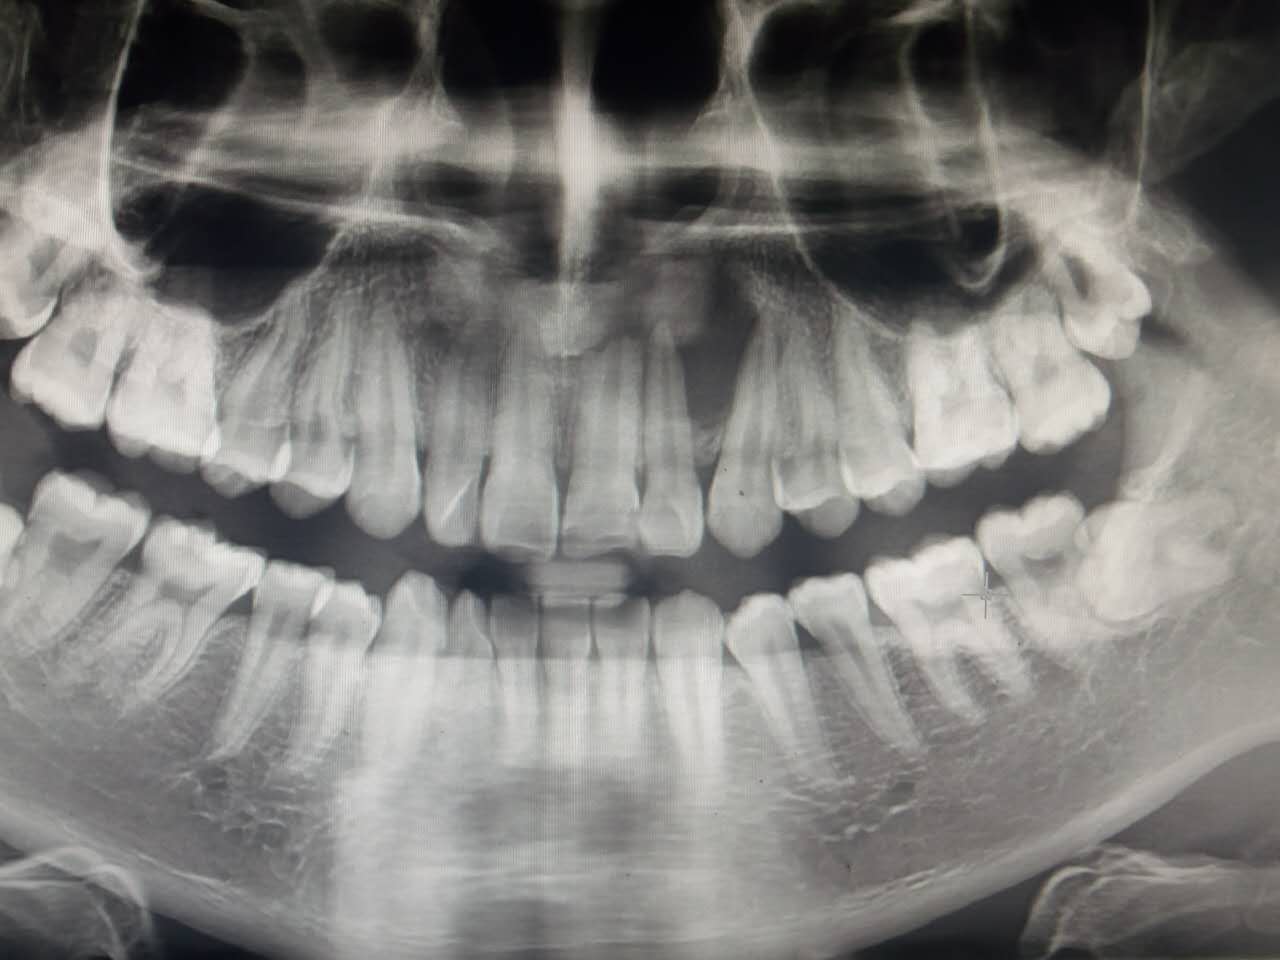

死髓牙2度,沒保留價(jià)值了,外傷造成的外吸收,即使到充也容易出問題。和患者溝通,要求做種植,用了兩個(gè)骨膠原,側(cè)切、尖牙沒事,側(cè)切做了一次根充